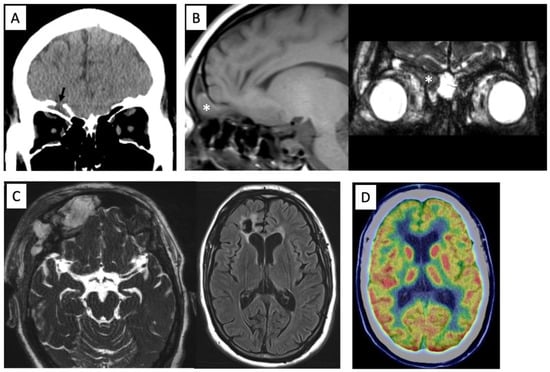

2. Case Presentation